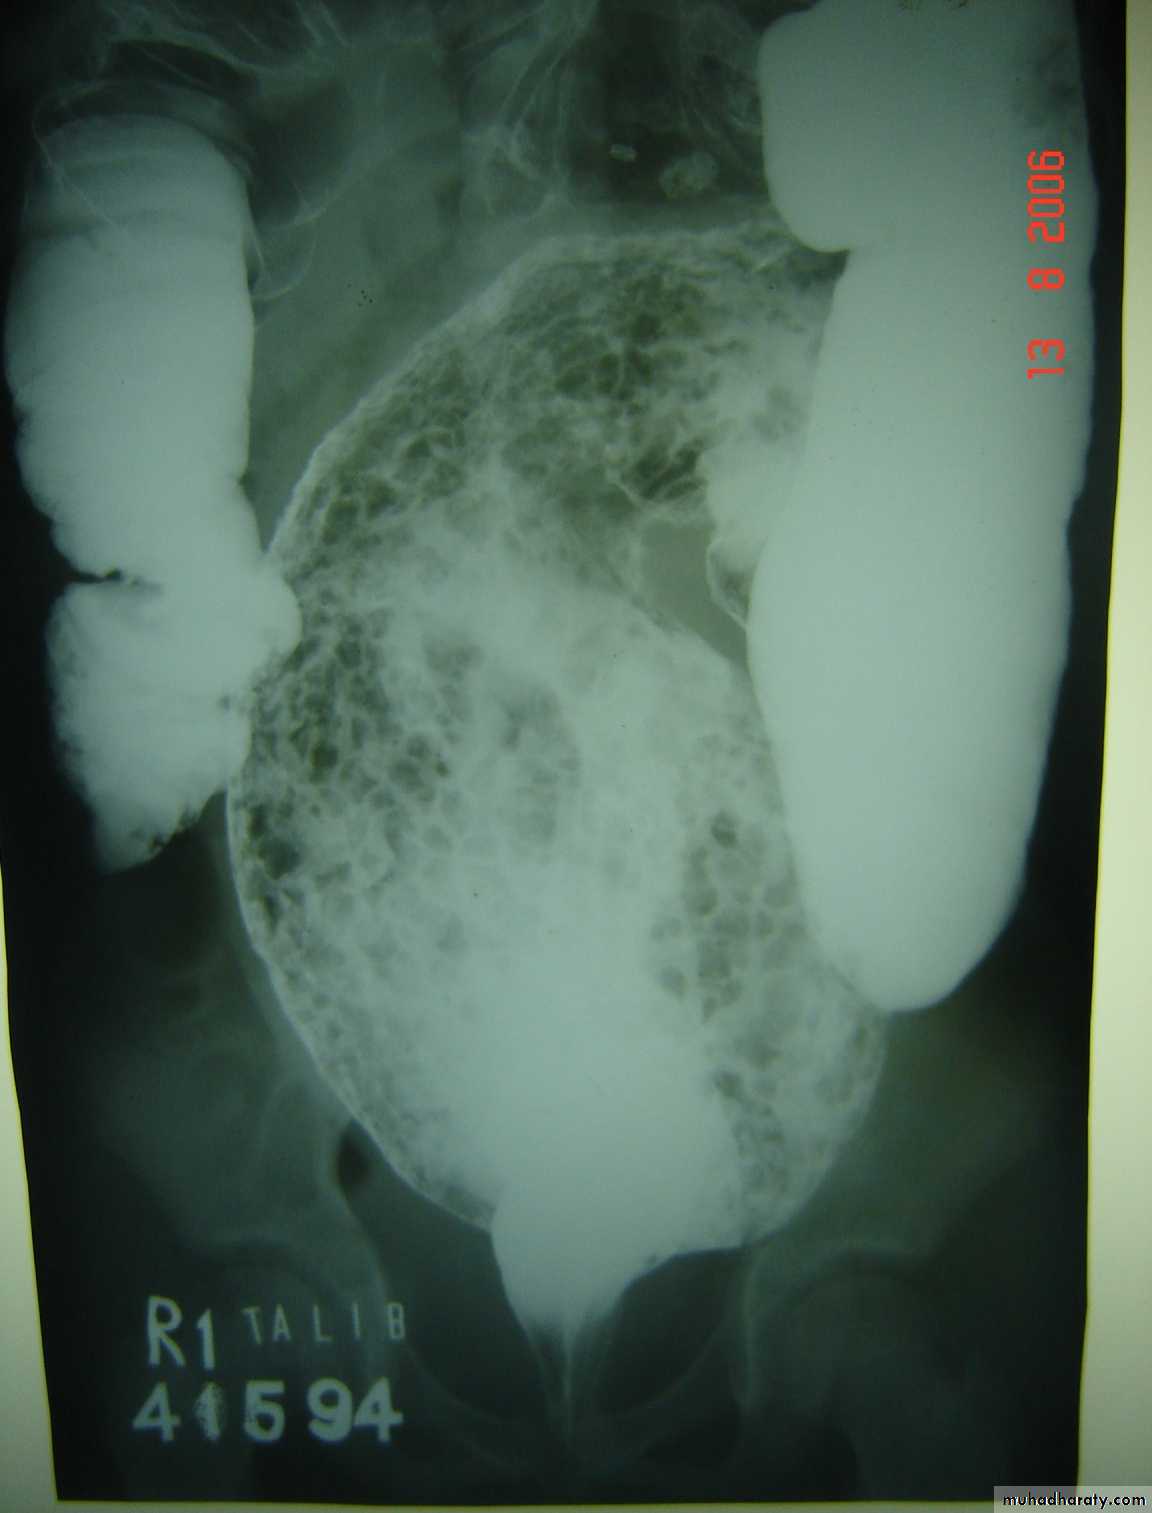

Intussusception